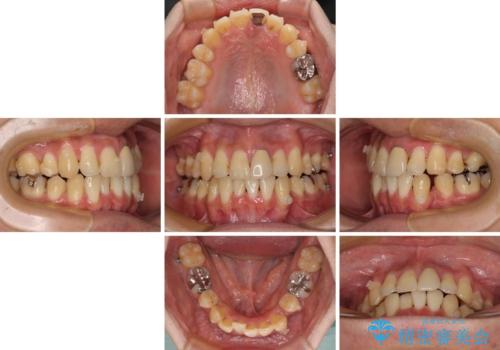

- 下顎の八重歯を気にして来院された患者様です。

左下以外、3本の第一小臼歯が既に抜去されており、左下は八重歯になっている状態でした。

左下の八重歯は手前に傾斜していたため、インビザラインによる抜歯矯正が可能と判断し、後方にある第一小臼歯を抜歯してインビザラインにて矯正治療を行うこととしました。

ワイヤー矯正と比較すると、八重歯が後方に傾斜した仕上がりとなりましたが、患者様ご希望のインビザラインにて十分な歯列を達成することができました。